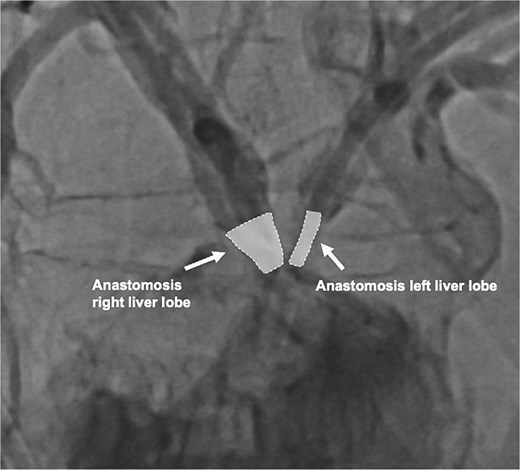

On the following day, a percutaneous transhepatic cholangiography drainage (PTCD) was placed in the right duct via interventional radiology for additional bile drainage support (Fig. 2). The patient was discharged on postoperative day 16 with the three closed drains in place. Four weeks later, she was readmitted for drain removal, with imaging (Fig. 3) and laboratory results (total bilirubin 8.4 μmol/L (norm <17 μmol/L) showing no signs of stenosis or leakage. After a follow-up of 18 months, the patient is in good condition with no clinical signs of late biliary complications.

Contrast-enhanced image of both hepaticojejunostomy anastomoses 4 weeks after biliary reconstruction.